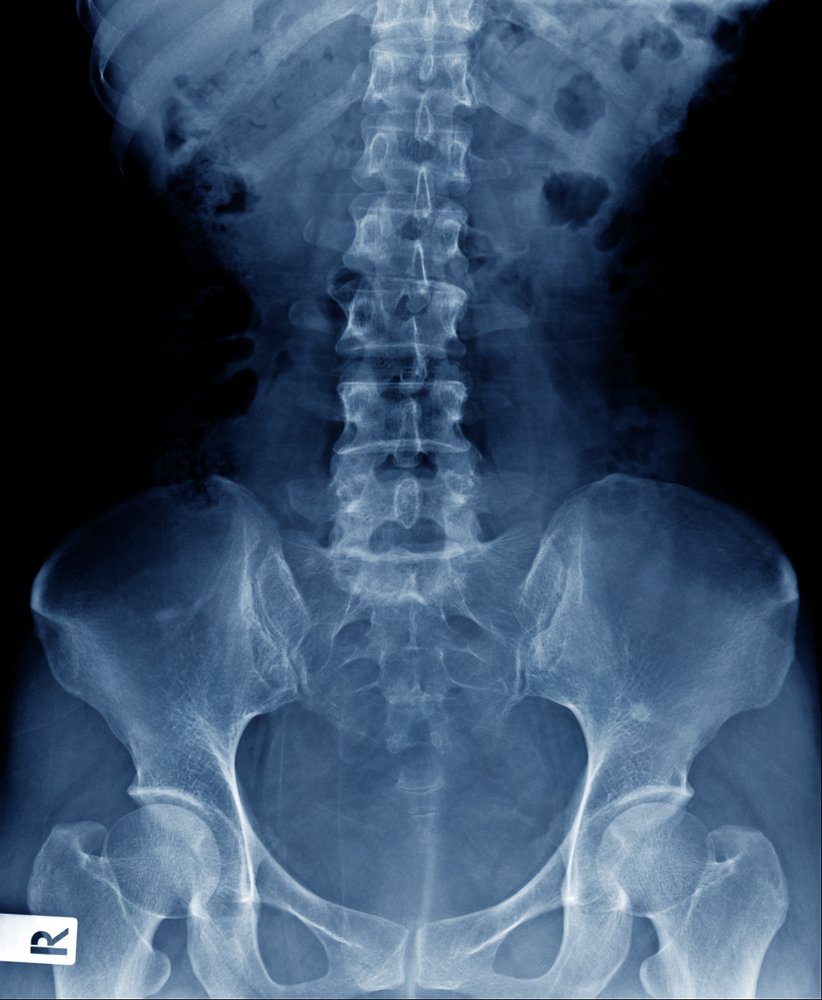

Kaulų retėjimą (osteoporozę) galima įvertinti įvairiais vaizdiniais tyrimais, tačiau įprasta rentgeno nuotrauka ne visada leidžia patikimai pastebėti ankstyvus pokyčius. Nors gydytojui kartais gali kilti įtarimas dėl sumažėjusio kaulų tankio apžiūrint stuburo ar klubo rentgenogramas, toks tyrimas paprastai nėra pakankamai tikslus ankstyvai osteoporozei prognozuoti, nustatyti ar patvirtinti.

Pagal dabartines medicinos žinias, kad įprastinis rentgenas aiškiau parodytų osteoporozę, kaulo mineralinio tankio sumažėjimas dažnai turi būti gana didelis – maždaug trečdalis ar daugiau. Dėl to vien rentgeno nuotraukomis remtis ankstyvoje stadijoje dažniausiai nepakanka.

Vis dėlto tradicinė rentgenografija yra labai naudinga kitose situacijose: ja dažnai nustatomi kaulų lūžiai, dantų ėduonis, plaučių uždegimas, virškinamojo trakto nepraeinamumas, kai kurie navikai, svetimkūniai ir kiti panašūs pakitimai.